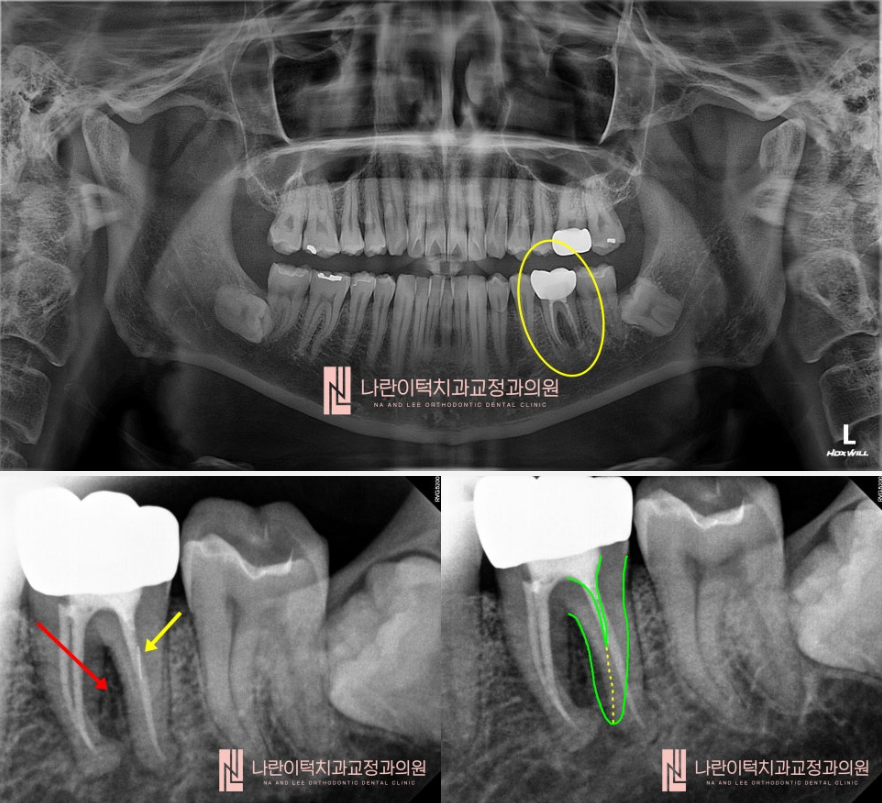

[초진 분석 Present Illness]

좌측 하악 첫번째 어금니(#36)의 두 다리 사이에 검은 음영(염증)이 보입니다.(빨간 화살표)

치아 내부에 파절 물질?처럼 의심되는 부위도 존재하네요. (노란 화살표)

신경치료전문의의 눈에는 찾지 못한 신경관(뿌리) 하나가 매직아이처럼 보입니다.

(초록 실선 + 노란 점선) 이 신경관 하나를 찾아서 잘 마무리 해주면 뿌리끝염증이 낫을 것 같습니다!

[치료 계획 수립Treatment Plan]

1.조심스럽게 크라운 제거

2. 조심스럽게 재신경치료 진행 (신경치료기구가 부러지지 않게 조심!)

3. 조심스럽게 찾지못한 신경관 찾기

4. 조심스럽게 뿌리끝 도달 후 염증 터트리기

5. 이차충치가 생기지 않도록 꼼꼼하게 레진코어올리기

6. 뿌리끝 염증 호전 양상을 파악하기 (6개월 이상)

7. 염증이 호전되는 사인이 보이면 크라운 올리기